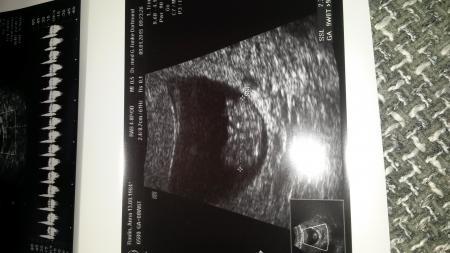

Hallo ihr Lieben! Bei mir wurde jetzt ab der 9 Woche vom Bauch aus geschallt! Nur kurz vaginal um die Gebärmutter/Hals zu begutachten! Man konnte Alles bestens erkennen, hätte ich auch nicht gedacht! Hier ein Foto!

Bild zu